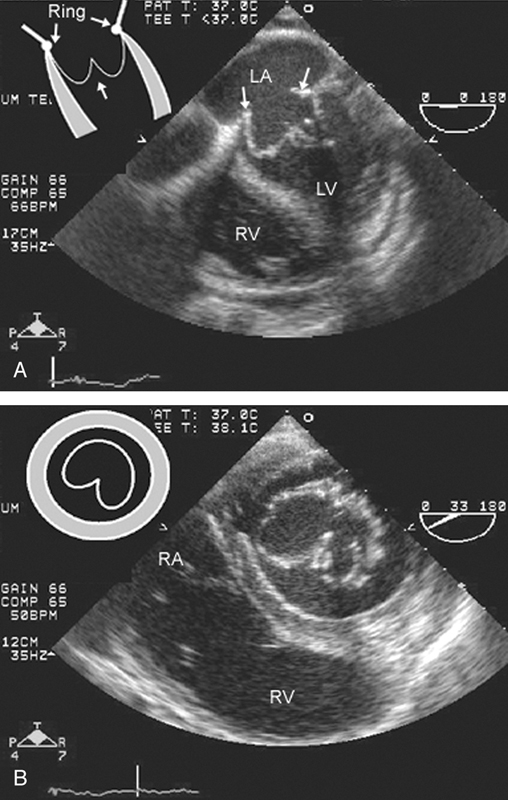

فحوصات تشخيصية لبعض امراض القلب والشرايين التاجية